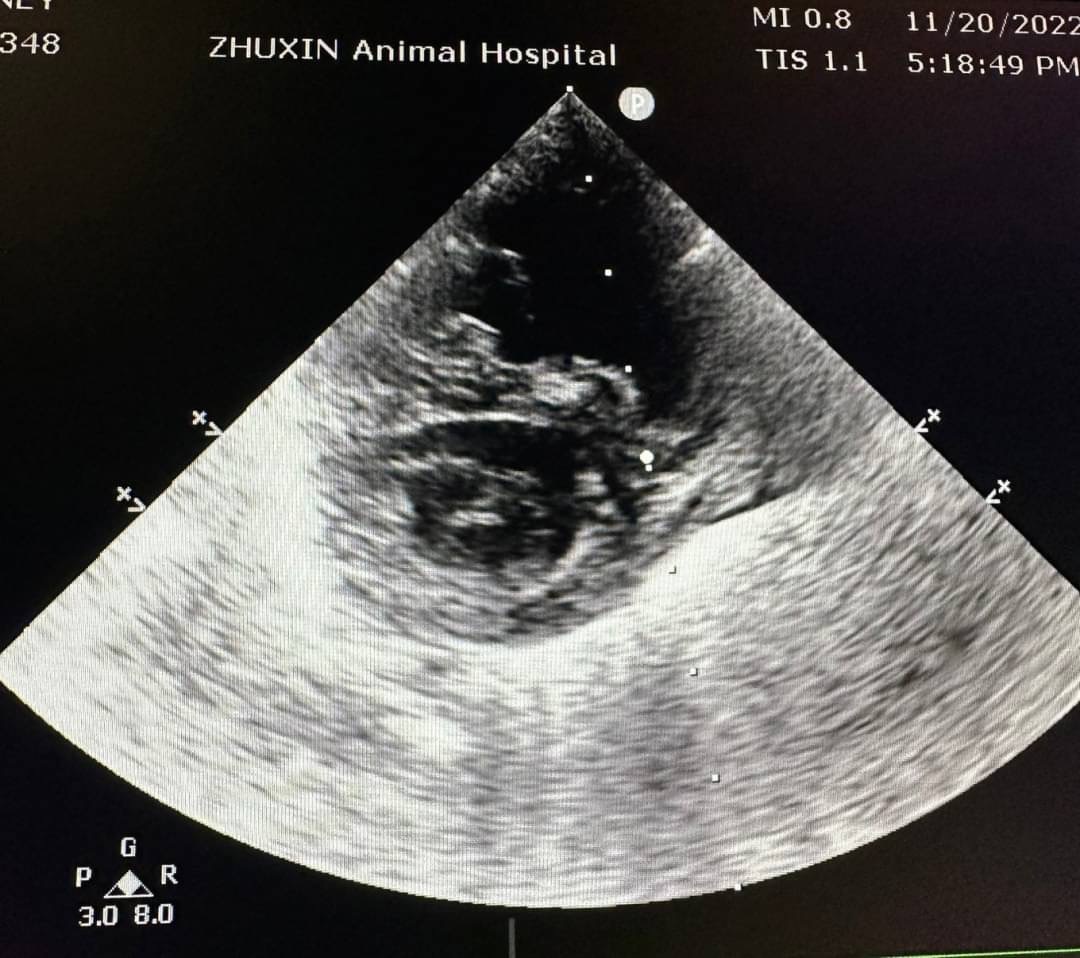

腹腔超音波下出現腹水,肝臟腫大伴隨肝門靜脈擴張。腹水檢測為漏出液,抹片下為少量發炎細胞,並無看到細菌。針對X光下心臟變大的影像,安排後續心臟超音波檢查,診斷為肺部高壓誘發肝門靜脈壓力上升引發腹水出現。心電圖下並無明顯心律不整。

而一般常使用心臟超音波參數和結構回推肺部壓力是否過大

如測量肺動脈或是三尖瓣逆流的流數,心臟結構的改變,如右心房擴張、右心室肥厚、收縮期中隔平坦、肺動脈擴張(PA:AO >1)等。